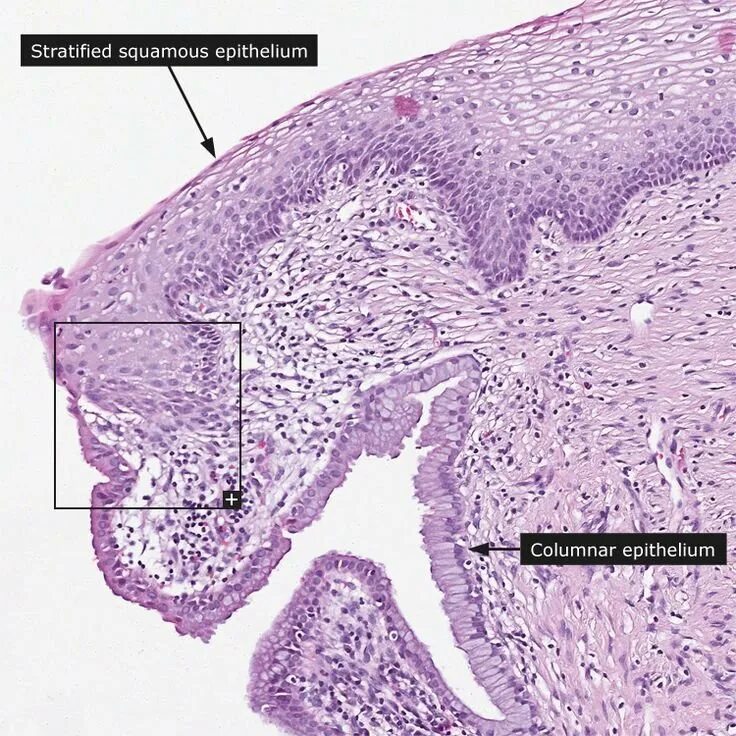

Гистология фиброзные фрагменты